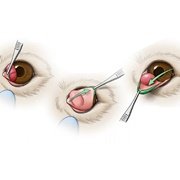

+ ศูนย์การผ่าตัดศัลยกรรมและบริการทันตกรรมสัตว์เลี้ยง กรุงเทพฝั่งธน

ให้บริการศัลยกรรมสัตว์เลี้ยง ทางด้านศัลยกรรมกระดูกและข้อ ศัลยกรรมระบบประสาท ศัลยกรรมโรคตาสัตว์

ศัลยกรรมเนื้องอกและมะเร็ง ศัลยกรรมทางด้านระบบสืบพันธ์ุ บริการด้านทันตกรรมสัตว์เลี้ยง เป็นต้น

โรงพยาบาลสัตว์เศรษฐกิจสัตวแพทย์ ได้ปรับปรุงห้องผ่าตัดและอุปกรณ์ตามมาตรฐานขั้นนำทางการสัตวแพทย์

ให้ทันสมัยเทียบเท่าห้องผ่าตัดในมนุษย์ และได้รวบรวมทีมสัตวแพทย์ศัลยกรรมชั้นนำระดับประเทศ เพื่อให้บริการกับสัตว์เลี้ยง

ที่ต้องการรักษาแก้ไขด้วยวิธีทางศัลยกรรม ให้มั่นใจว่า “ลูกๆ” ของท่านจะปลอดภัยสูงสุดเมื่อต้องผ่าตัด